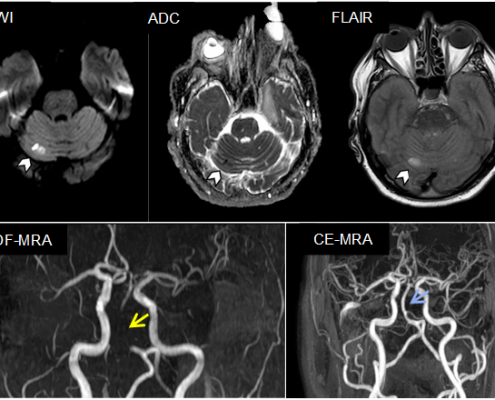

Lara Le Noan2021-06-04 08:01:372021-06-03 08:21:26An uncommon pitfall in diagnosing basilar artery occlusion